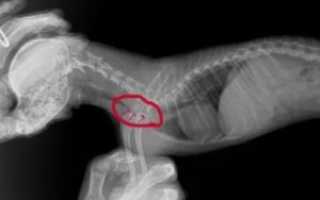

Для подтверждения диагноза необходима рентгенограмма трахеи в боковом положении. Желательно сделать снимки на фазе вдоха и выдоха – это связано с тем, что во время вдоха происходит коллапс шейного отдела, а при выдохе коллапс грудного отдела. В тяжелых случаях сужение трахеи или провисание дорсальной мембраны визуализируются и на обычных снимках.